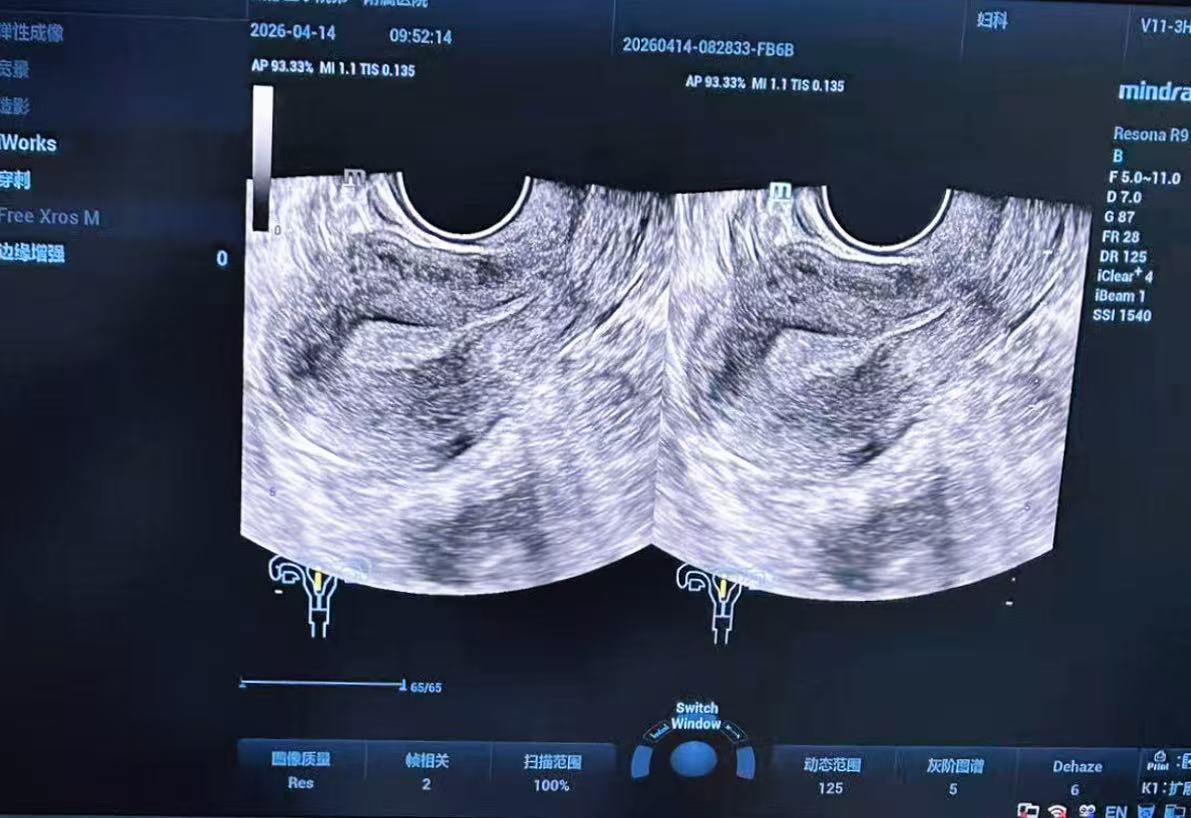

“作为健康管理从业者,我深知对于50岁以上的女性而言,每年进行经阴道的子宫超声检查并非只是‘走个流程’,而是守护生命的重要底线。”近期,成都某医院主治医生李某(化名)陪同65岁的母亲进行年度常规体检时,经阴道子宫超声检查发现了异常回声。经进一步诊断,确诊为I期(早期)子宫内膜癌。由于发现及时,目前老人已通过微创手术完成干预,顺利出院,且出院后无需进行放疗、化疗等其他治疗,预后效果极佳,几乎不影响寿命。

图:超声检查

“超声检查会受到房间光线、设备、操作技巧、辨图经验等因素的影响,同时,超声波自身存在局限性,易受腹部气体影响成像质量。选择经阴道超声检查能够获得更优质的声像图,特别是在健康人群中发现初期细微的声像图变化,具有极高的价值。在子宫内膜癌的筛查中,高分辨率经阴道超声是国际公认的首选影像学方法。我院配备的高品质彩色多普勒超声诊断仪,能够清晰显示绝经后女性子宫内膜厚度及血流信号,从硬件层面最大程度降低了漏检率。